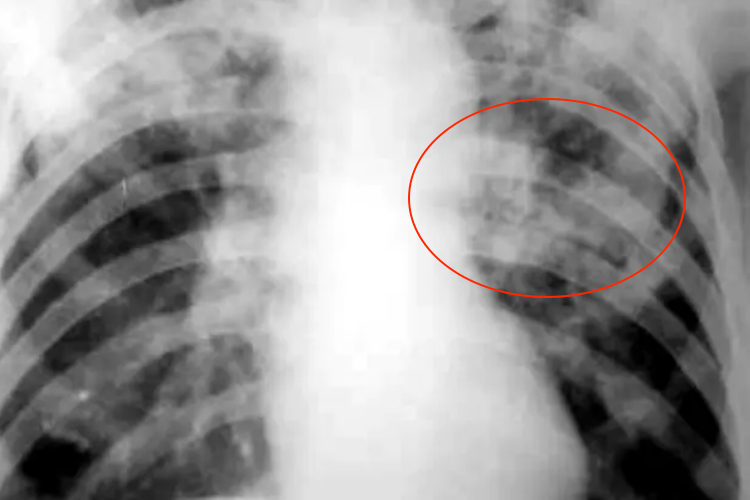

干酪性肺炎:呈大叶性密度均匀磨玻璃状阴影,逐渐出现溶解区,呈虫蚀样空洞,可出现播散病灶。有时也可呈小叶斑片播散病灶,多发生在双肺中下部。

纤维空洞型肺结核:双侧或单侧肺野出现纤维厚壁空洞和广泛的纤维增生,造成肺门抬高和肺纹理呈垂柳样。